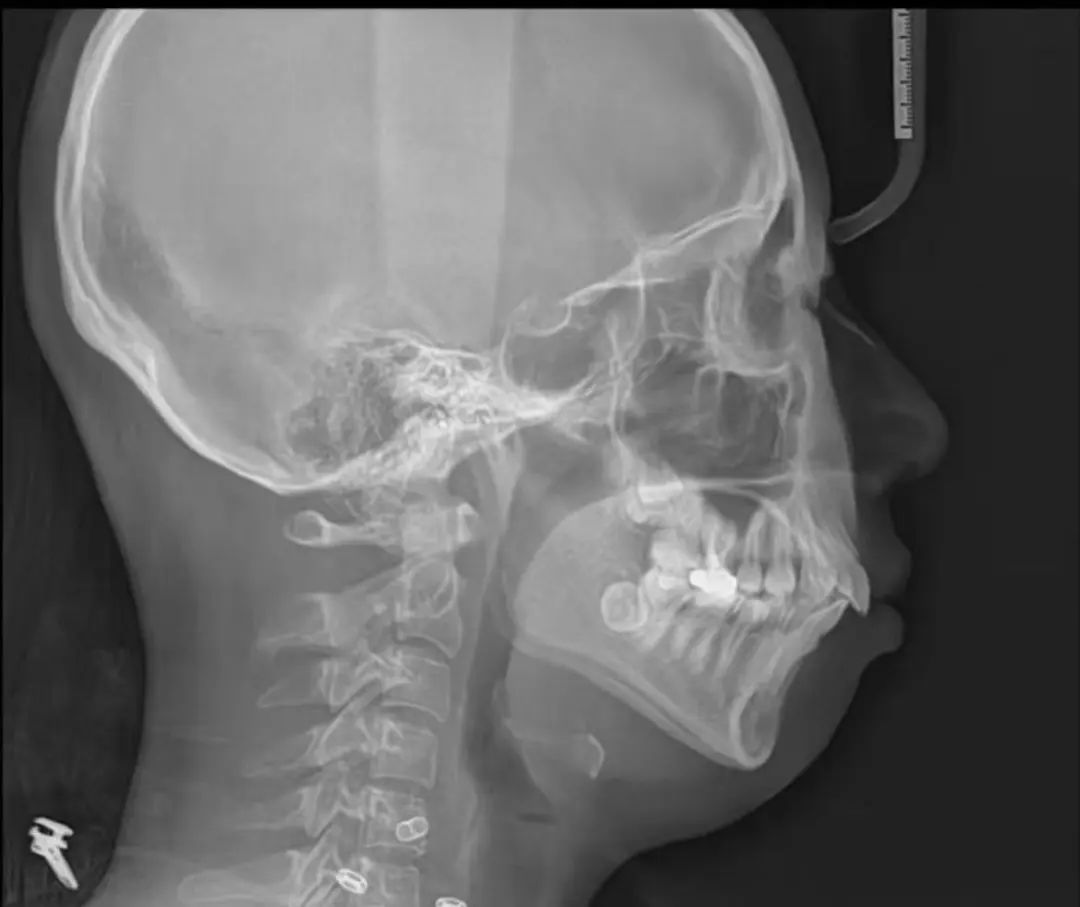

下颌后缩如何诊断

通过拍摄侧位片然后进行头影测量分析,可以更准确地评估下颌与颅骨的关系,确定下颌后缩的程度。